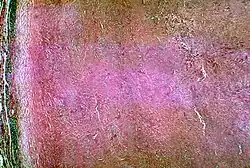

Histopathological changes in a case of coccidioidomycosis of the lung showing a large fibrocaseous nodule.

Rain starts the cycle of initial growth of the fungus in the soil.[17] In soil (and in agar media), Coccidioides exist in filament form. It forms hyphae in both horizontal and vertical directions. Over a prolonged dry period, cells within hyphae degenerate to form alternating barrel-shaped cells (arthroconidia) which are light in weight and carried by air currents. This happens when the soil is disturbed, often by clearing trees, construction, or farming. As the population grows, so do all these activities, causing a potential cascade effect. The more land that is cleared and the more arid the soil, the riper the environment for Coccidioides.[18] These spores can be easily inhaled unknowingly. On reaching alveoli, they enlarge in size to become spherules, and internal septations develop. This division of cells is made possible by the optimal temperature inside the body.[19] Septations develop and form endospores within the spherule. The rupture of spherules releases these endospores, which in turn repeat the cycle and spread the infection to adjacent tissues within the infected individual's body. Nodules can form in the lungs surrounding these spherules. When they rupture, they release their contents into the bronchi, forming thin-walled cavities. These cavities can cause symptoms including characteristic chest pain, coughing up blood, and persistent cough. In individuals with a weakened immune system, the infection can spread through the blood. The fungus can also, rarely, enter the body through a break in the skin and cause infection.[19]